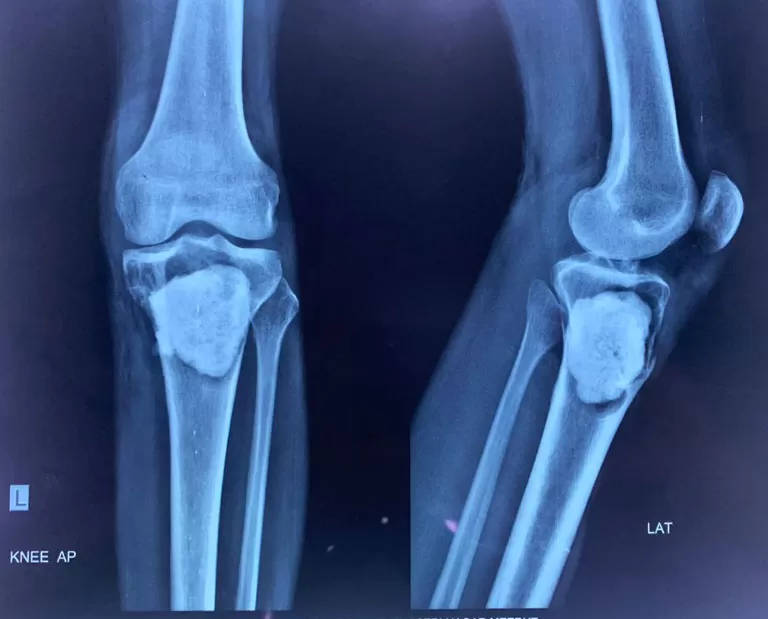

Mr. Rohtash

Name: Mr. Rohtash

Date of Operation: 17 Mar 2021

Age: 45 Years

Mobile No: 98885 35038